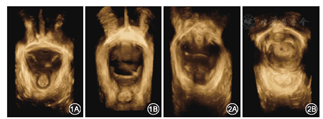

对照组静息状态时,肛提肌裂孔呈菱形,结构紧凑完整,肛提肌裂孔内尿道、阴道、直肠从前至后呈直线依次排列,两侧耻骨直肠肌对称且回声连续;最大Valsalva动作时,肛提肌裂孔提肌纤维被动牵拉并扩张,肛提肌裂孔增大(图1)。病例组静息状态时,结构较对照组疏松,内回声减低;最大Valsalva动作时,肛提肌裂孔明显增大(图2)。本研究中5例患者还可观察到单侧或双侧耻骨直肠肌回声不连续(图3)。